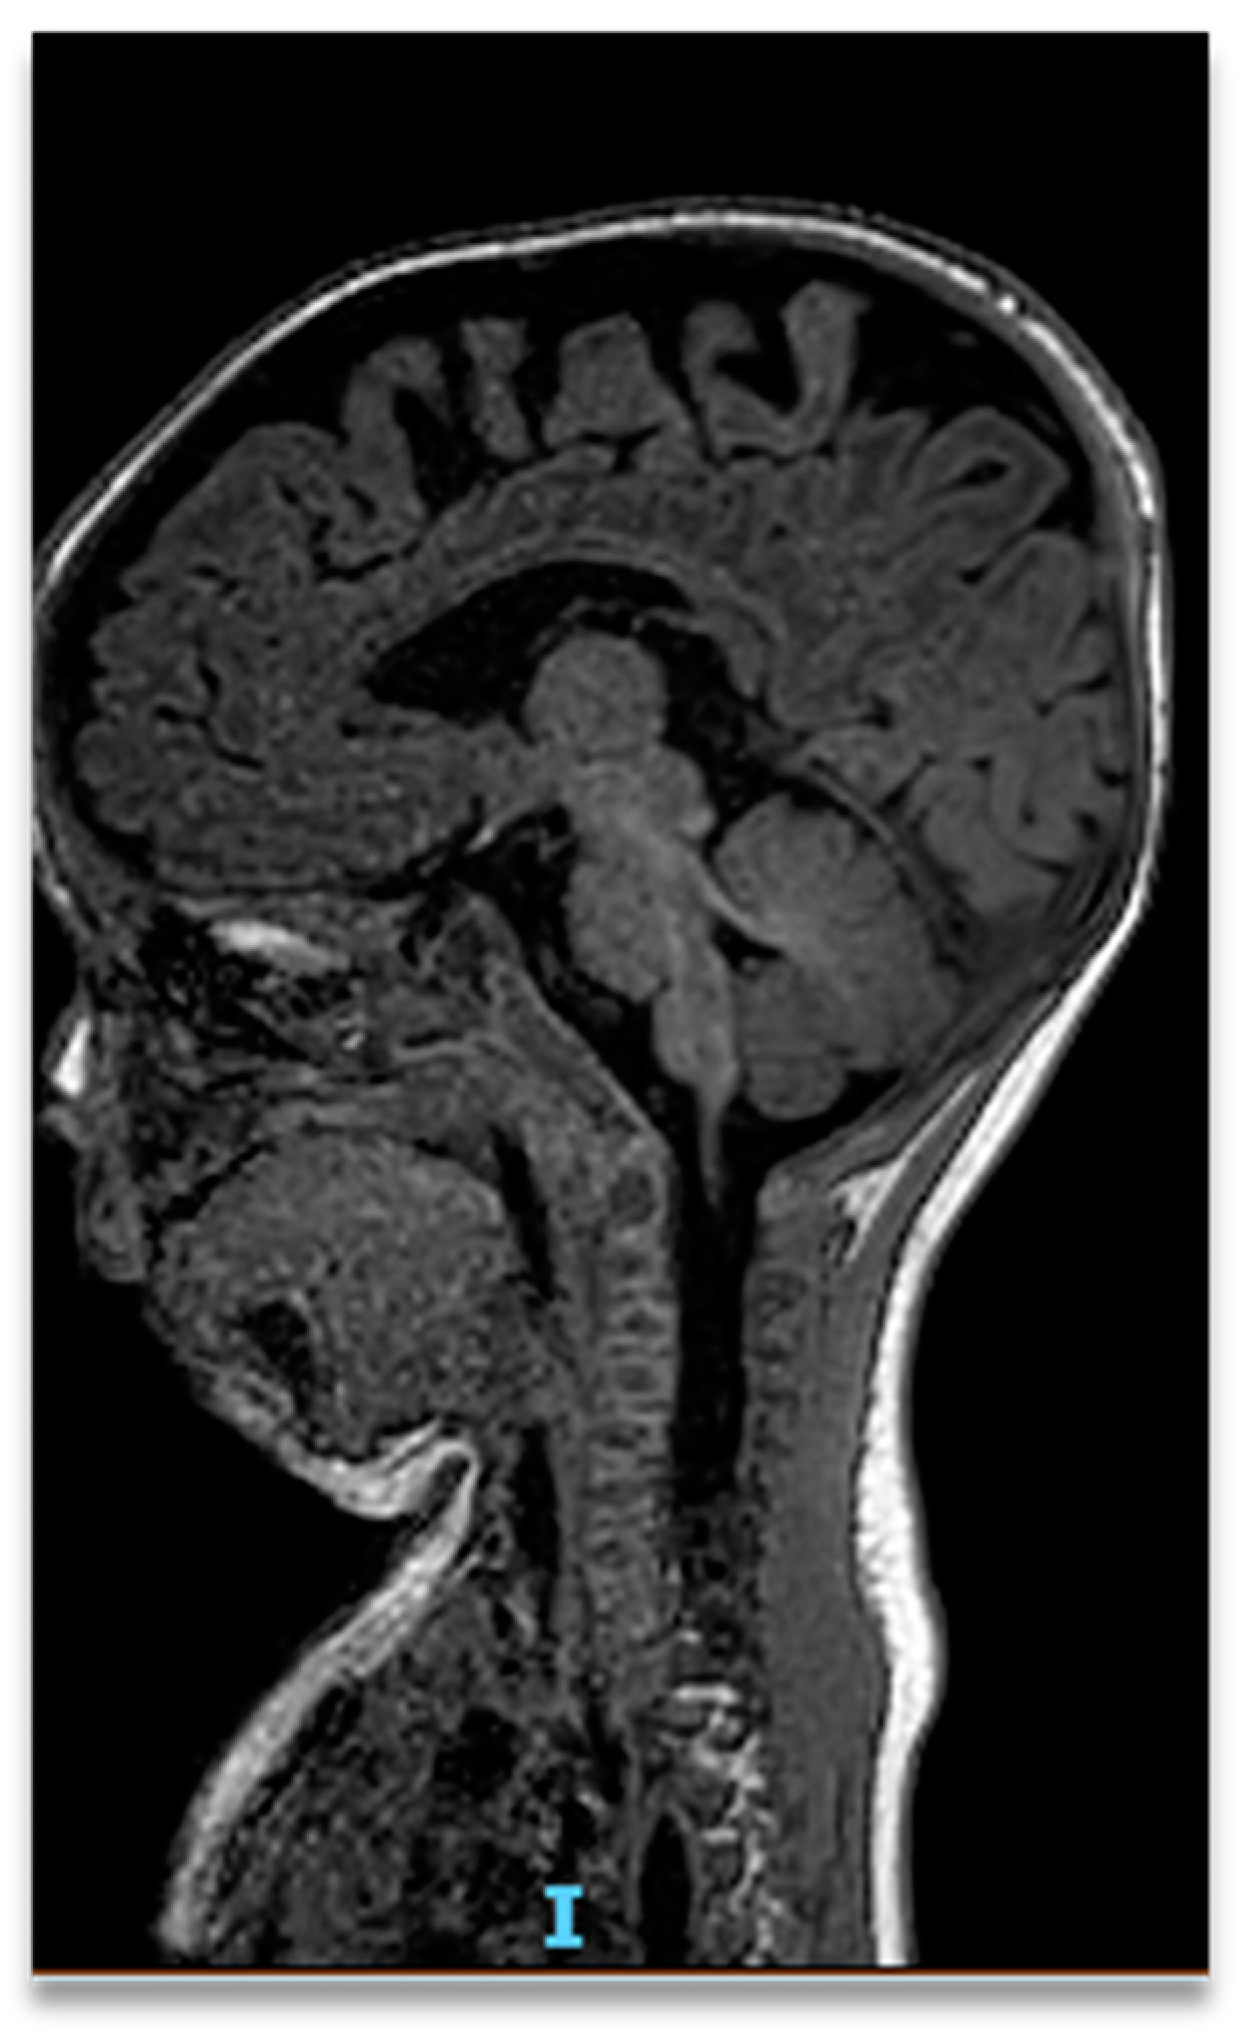

2. Case Report